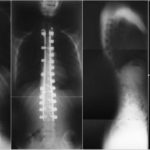

Erişkin Tip Skolyozda Cerrahi Ne Zaman Önerilir?

Erişkin tipi olan skolyozlarda ilk tedavi yöntemi olarak enjeksiyon, korse, fizik tedavi ve rehabilitasyon, ağrı kesiciler verilir. Ancak bu uygulamalar şikayetleri azaltmadıysa bu durumda cerrahi düşünülmektedir.

Hastanın ayaklarında ya da bacaklarına başlayan güçsüzlükle beraber yürüyüş mesafesine sürekli olarak azalması ve ilerleyen derecelerden biri olan idrar kaçırması gibi şikayetler gelişirse erişkin yaşta skolyoz tedavisi olarak cerrahi büyük bir oranda düşünülmeye başlanır.